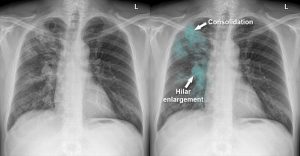

روشهای تشخیص سل ریه

تشخیص سل نیازمند بررسی دقیق توسط پزشک متخصص ریه است. مهمترین روشهای تشخیصی عبارتند از:

عکسبرداری از قفسه سینه (X-ray)